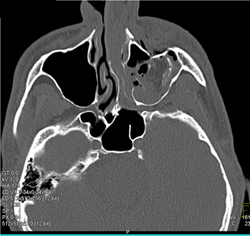

Fractured Wall of Sinus With Bleed